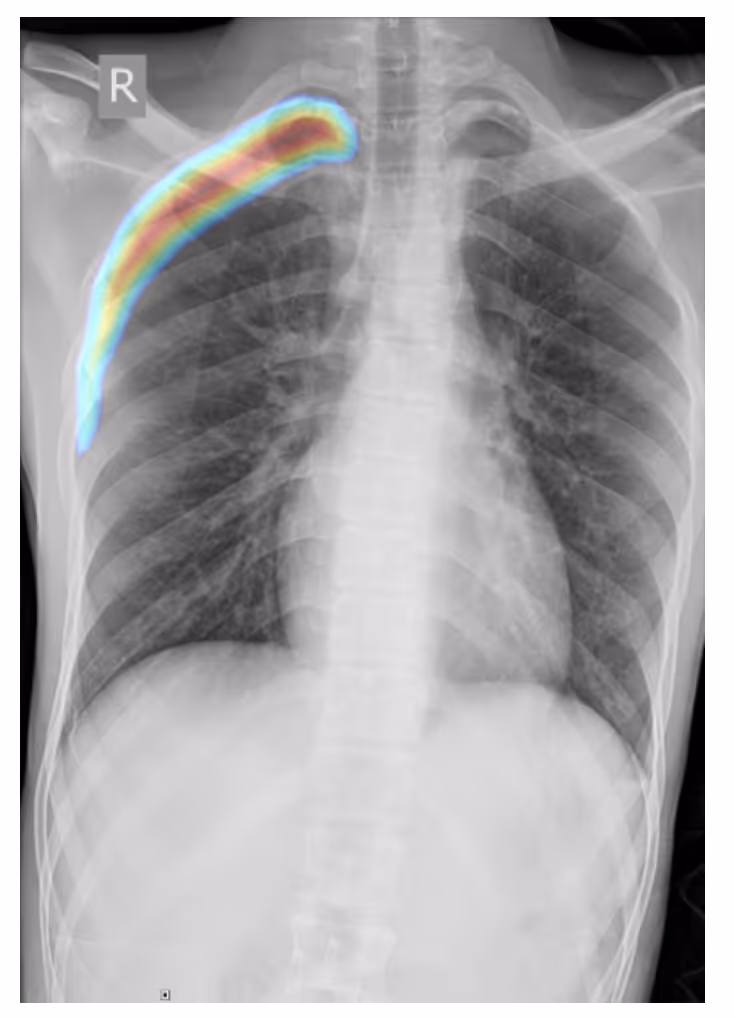

- A frontal chest radiographic image highlights the classic appearance of right-sided pneumothorax with a readily apparent visceral pleural line as seen without distal lung markings

ConclusionPhysicians can use DrAid for re-checking diagnostic results, thereby supporting the quality and efficiency of doctor performance.Interested in deploying DrAid at your health facility?Contact the Ferrum Health team to learn more.